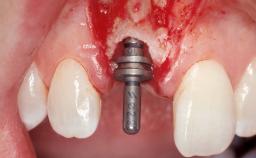

Immediate Flapless Placement of an Implant in a Maxillary Left Central Incisor Site

Placement Protocol Immediate implant placement

Tooth Site Maxillary incisor or canine

Socket Morphology Single-root socket

Socket Integrity Damage to one or more bone walls

Bone Volume Damage to one or more socket walls

Complexity Moderate

Risk of Complications High